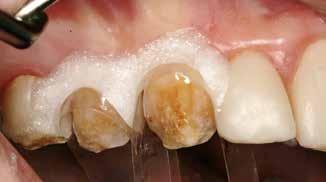

Fugtighedskontrol

Fig. 3. Kofferdam blev anlagt sektionsvis for at opnå god fugtighedskontrol. Fig. 3. Rubber dam was applied section wise to achieve appropriate moisture control.

okklusal-vertikale dimension. De afficerede dentinoverflader blev ridset i overfladen med en grov diamant, men derudover blev der ikke foretaget nogen form for kavitetspræparation, da intentionen var at gennemføre en minimalt invasiv behandlingstilgang. Kofferdam blev anlagt i hvert arbejdsfelt (Fig. 3) og adhæsivet påført med en æts-og-skyl-strategi (ætsning af emalje og dentin, primer, adhæsiv). Derefter blev tænderne bygget op med en mikrohybrid komposit for at genskabe tandens naturlige form (Fig. 4). I underkæbefronten blev der kun lagt et tyndt lag med komposit pga. pladsmangel. Efter omhyggelig pudsning og polering havde patienten okklusion på samtlige tænder og var tilfreds med både funktion og æstetik.